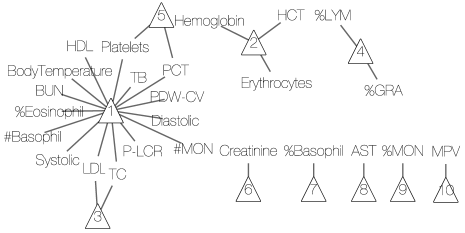

We consider two simulation scenarios. In both scenarios, we generate the patient-disease matrix from an IBP() model with and sample size . The resulting matrix has columns and rows, displayed in Figure 5(b). Given , we generate a binary symptom-disease matrix and a categorical symptom-disease matrix with in the following manner. We first set for and , for and . We then randomly change 10% of the zero entries in to 1 and 10% of the zero entries in to +1 or -1. The resulting matrices and are shown in Figures 5(c) and 5(d).

In Scenario I, the observations and are generated from the sampling model i.e. equations (4) and (5). To mimic the Chinese EHR data, we assume that we have diagnoses for the first disease and that we know the related symptoms for the first disease. In the model, we therefore fix the first column of , and to the truth. In addition, we assume that we have partial information about the second latent disease: the symptom-disease relationships are known, but no diagnostic information is available. Accordingly, we will fix the second columns of and , but leave the second column of as unknown parameters. We ran the MCMC algorithm described in Section 4 for 5,000 iterations, which took minutes on a desktop computer with a 3.5 GHz Intel Core i7 processor. The first half of the iterations are discarded as burn-in and posterior samples are retained at every 5th iteration afterwards.

Inference summaries are reported in Figure 5. Figure 5(a) shows the posterior distribution of the number of latent diseases. The posterior mode occurs at the true value . Conditional on , the posterior point estimate is displayed in Figure 5(e) with mis-allocation rate 111The percentage is computed based on free parameters in only.. Conditional on , the point estimates and are provided in Figures 5(f) and 5(g). The similarity between the heatmaps of the simulation truth and estimates indicates an overall good recovery of the signal. The error rates in estimating and are 0% and 2%, respectively. We repeat this simulation 50 times. In 96% of the repeat simulations, we correctly identify the number of latent diseases; in the remaining 4%, it is overestimated by 1. When is correctly estimated, the average mis-allocation rate, error rates for and are 3%, 1% and 1% with standard deviation 0.5%, 1% and 1%, respectively. We provide addtional simulation studies in Supplementary Material A to investigate the performance of DFA with different hyperparameters and with the alternative prior that was introduced in (3).

We repeat the experiment 50 times for . The estimated across 50 simulations are plotted in Figure 5(h). We observe that DFA tends to overestimate when model is misspecified. We report the performance of estimating and based on the best subset of columns. The mean (standard deviation) error rates in estimating and are 8% (4%) and 9% (3%), respectively. SLFM has slightly higher error rates, 12% (1%) and 11% (1%).